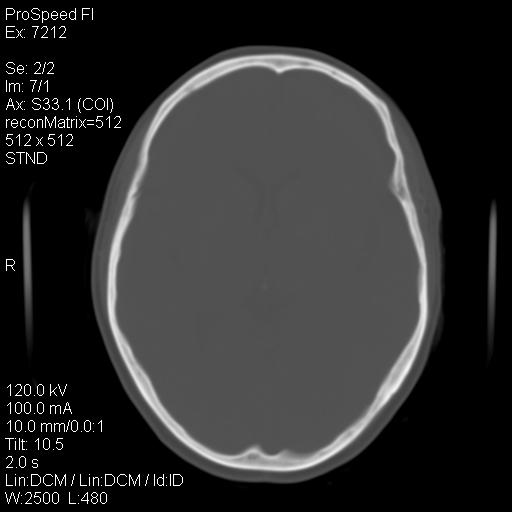

标题: CT18636:F 44Y,头痛三个月,左侧肢体麻木一周。临床诊断, [打印本页]

标题: CT18636:F 44Y,头痛三个月,左侧肢体麻木一周。临床诊断,

额顶骨多发穿凿样骨缺损区,不排除骨髓瘤等改变,进一步检查。

额顶骨多发穿凿样骨缺损区,不排除骨髓瘤或嗜酸性肉牙肿等改变,进一步检查。

1)考虑左侧额部慢性硬膜下血肿(或硬膜下积液)。2)颅骨骨髓瘤不排除;建议行进一步检查。

1)考虑左侧额颞部及右侧额部慢性硬膜下血肿(或硬膜下积液)。2)颅骨骨髓瘤不排除;建议行进一步检查。

2)颅骨骨髓瘤不排除;建议行进一步检查。

1)右侧半卵圆中心腔隙性脑梗塞。2)考虑左侧额部慢性硬膜下血肿(或硬膜下积液)。3)颅骨骨髓瘤不排除;建议行进一步检查。